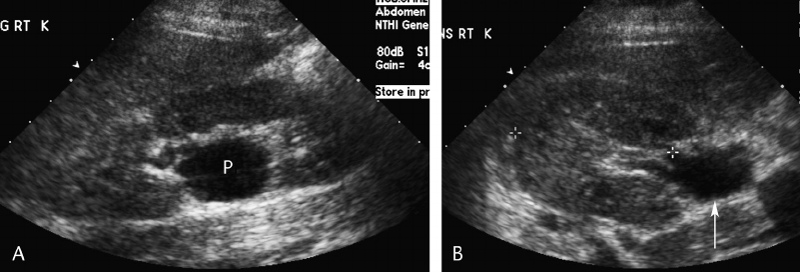

Pancreatic Psydocyst

Spherical fluid collection of pancreatic enzymes that arise from inflamatory, necrotic and hemorrhage processes of the pancrreas

persistently elevated amylase and lipase

Pancreatic Psydocyst

Spherical fluid collection of pancreatic enzymes that arise from inflamatory, necrotic and hemorrhage processes of the pancrreas

persistently elevated amylase and lipase

Pancreatic Psydocyst

Spherical fluid collection of pancreatic enzymes that arise from inflamatory, necrotic and hemorrhage processes of the pancrreas